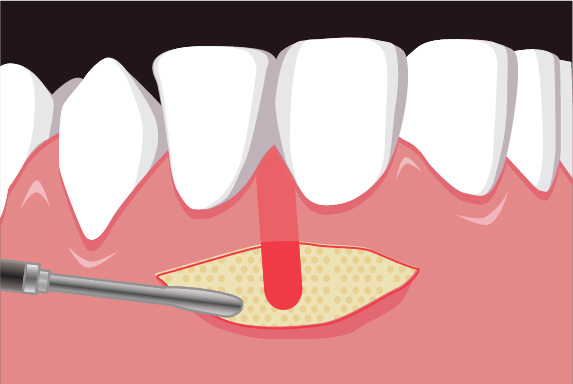

理事長の菅は日々新たな歯科治療の技術や知識を学び、それを臨床の現場に反映しています。再生療法の世界的な権威のDr. Cortellini 歯周組織再生治療のセミナーを受講。

また、トロント大学での1年間の根管治療スタディプログラムの受講や歯周再生マスターコース受講、テキサス大学ヒューストン校の歯周病コース修了、日本口腔インプラント学会専門医、AAID(アメリカのインプラントにおける最難関資格)の専門医資格を取得しております。

専門医資格を持つ医師が歯周組織再生治療を手がけるので、安心して治療を受けていただけます。